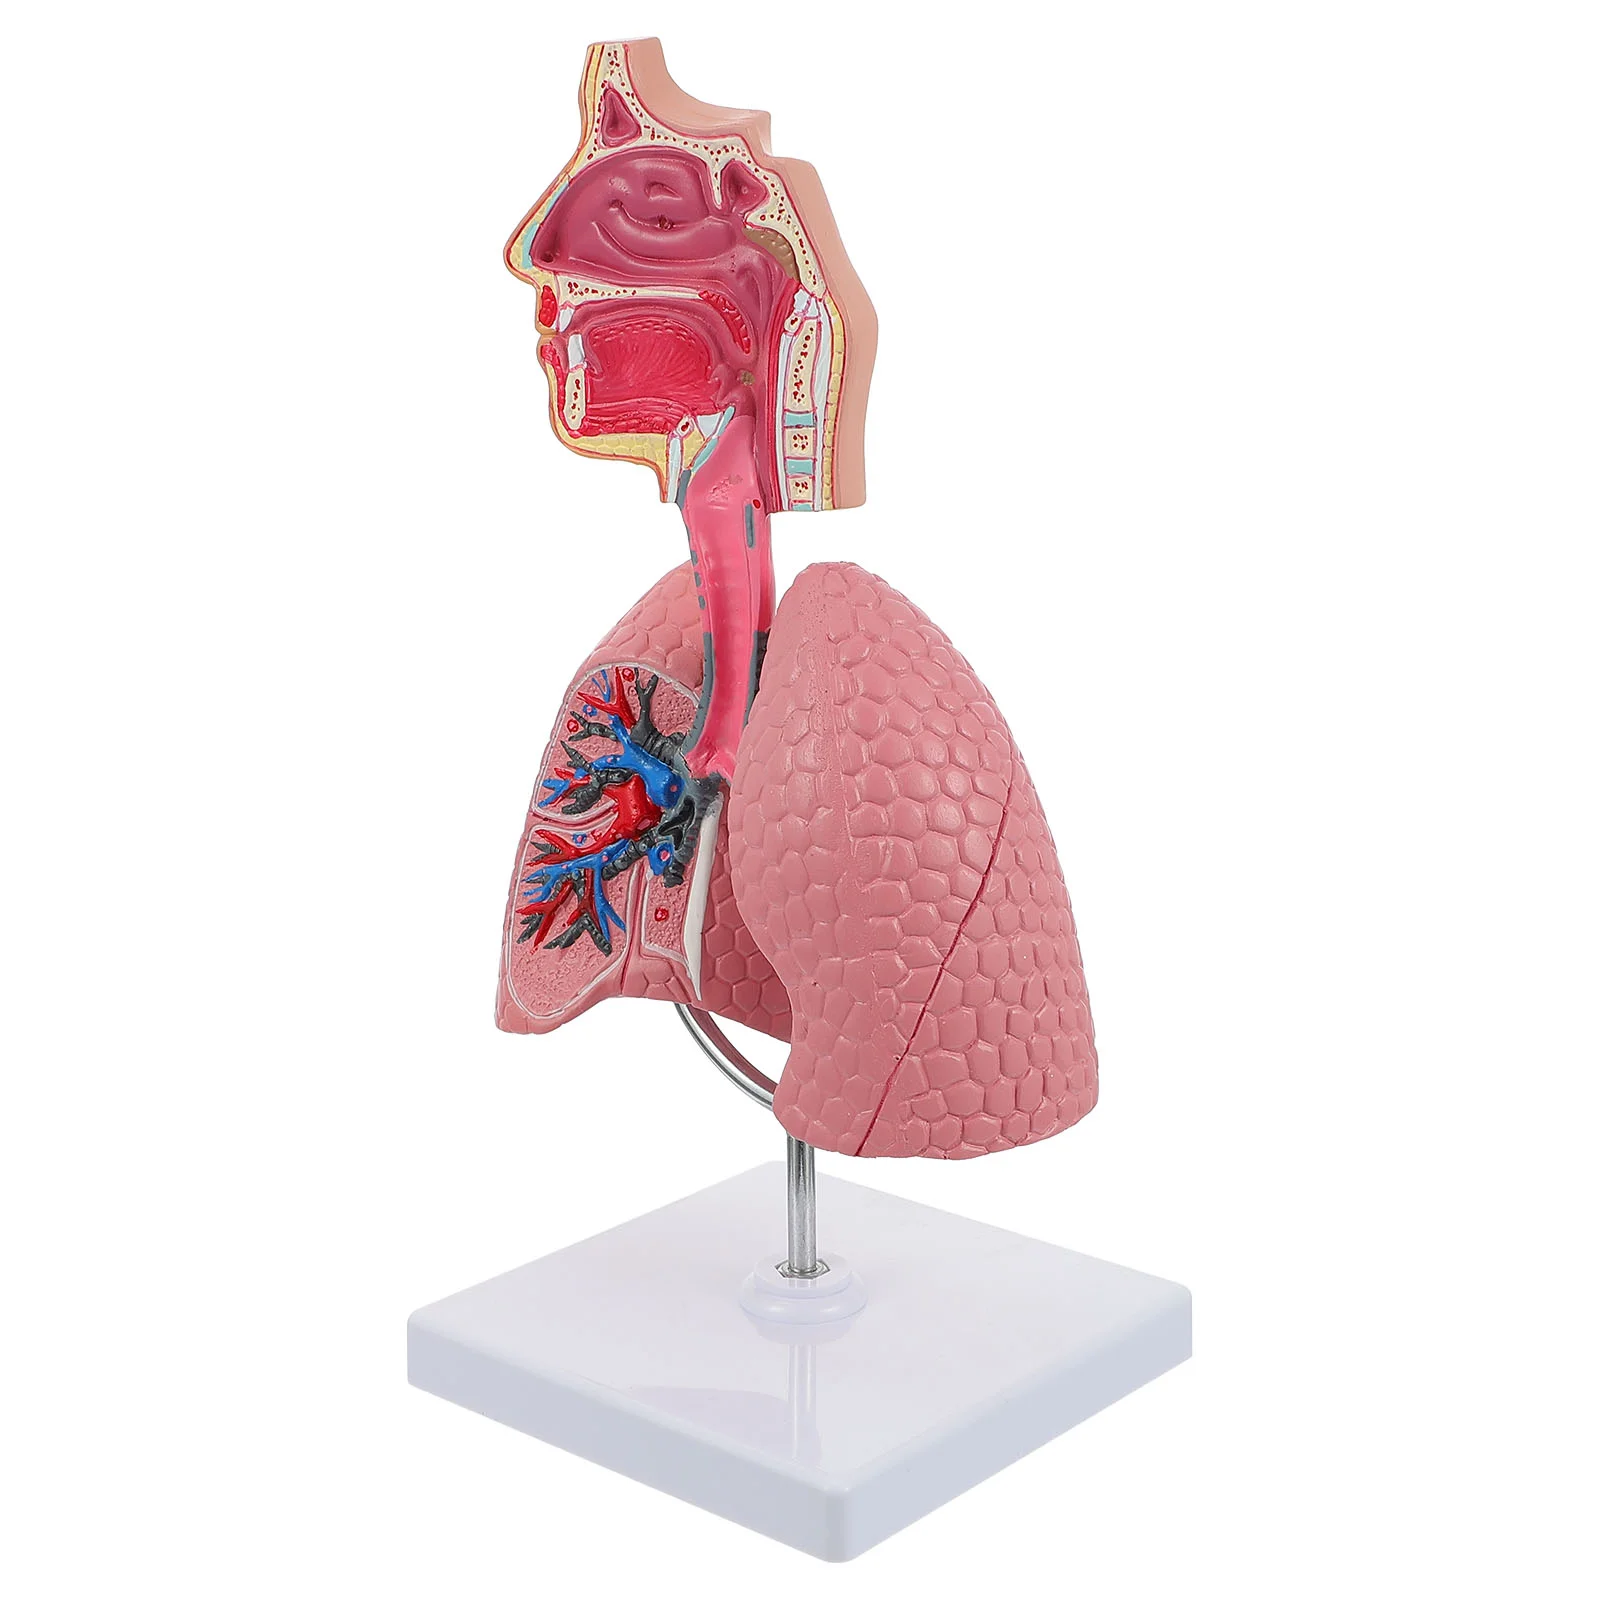

Human Respiratory System Anatomy Model

Купить за 27350 RUR

Следите за акциями и распродажами в июле 2026 от ООО ДЖУМ ИНН 7714448295 , www.joom.ru.

Lung Respiratory Anatomy Model Teaching System Human Display model School Lungs Anatomical Heart Educational Nasal Toy

Купить за 25305.55 RUR

Следите за акциями и распродажами в июле 2026 от aliexpress.com/..

Lung Respiratory Anatomy Model Teaching System Human Display model School Lungs Anatomical Heart Educational Nasal Toy

Купить за 25270.74 RUR

Следите за акциями и распродажами в июле 2026 от aliexpress.com/..

Lung Respiratory Anatomy Model Teaching System Human Display model School Lungs Anatomical Heart Educational Nasal Toy

Купить за 21998.45 RUR

Следите за акциями и распродажами в июле 2026 от aliexpress.com/..

Lung Respiratory Anatomy Model Teaching System Human Display model School Lungs Anatomical Heart Educational Nasal Toy

Купить за 20234.81 RUR

Следите за акциями и распродажами в июле 2026 от aliexpress.com/..